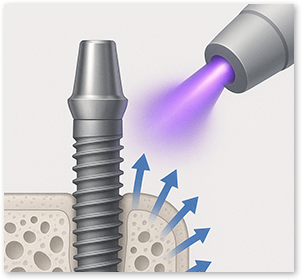

During manufacturing, shipping, and long-term storage,

hydrocarbons can build up on the implant surface over time,

which may reduce biocompatibility.

Plasma implants use high-energy plasma

to remove hydrocarbons

and reactivate the surface for higher biocompatibility.

During manufacturing, shipping, and long-term storage, hydrocarbons can accumulate on the implant surface, reducing biocompatibility. Plasma implants remove hydrocarbons with high-energy plasma and reactivate the surface for higher biocompatibility.

Faster Bone Integration

Plasma cleaning activates the surface → faster bone bonding → shorter recovery

Better Biocompatibility

Plasma treatment improves surface hydrophilicity → promotes blood and protein adhesion → an implant the body accepts more easily

Creating a safer implant surface through removal of surface impurities

Improved early protein attachment through organic removal and surface activation